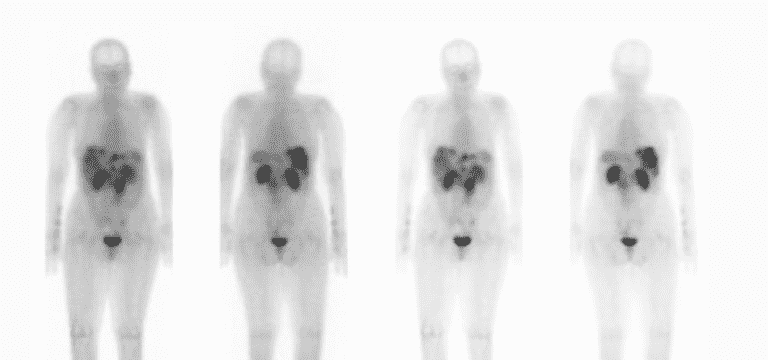

Octreotide – it is an octapeptide that is synthetic analogue of somatostatin. A radio-labeled form of octreotide ((68Ga-DOTA-Nal3) - Octreotide) is injected into the body intravenously when octreotide scan is performed. This attaches to somatostatin receptors on tumor cells.

A device detects radio-labeled octreotide in body, thereby detecting tumor cells in the body.

Octreotide scan is done to screen for carcinoid tumor and other types of neuroendocrine tumors. Neuroendocrine tumors arise from neuroendocrine cells of 17 types.